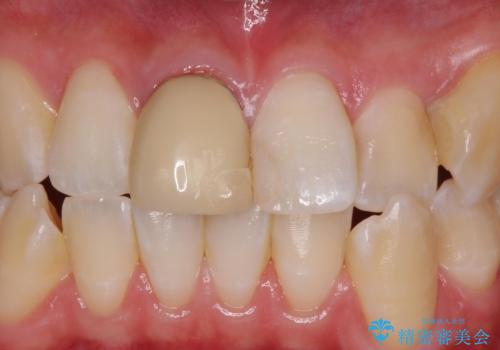

Dr. 岡田康成の症例写真

担当医 岡田康成<2025年8月25日更新>